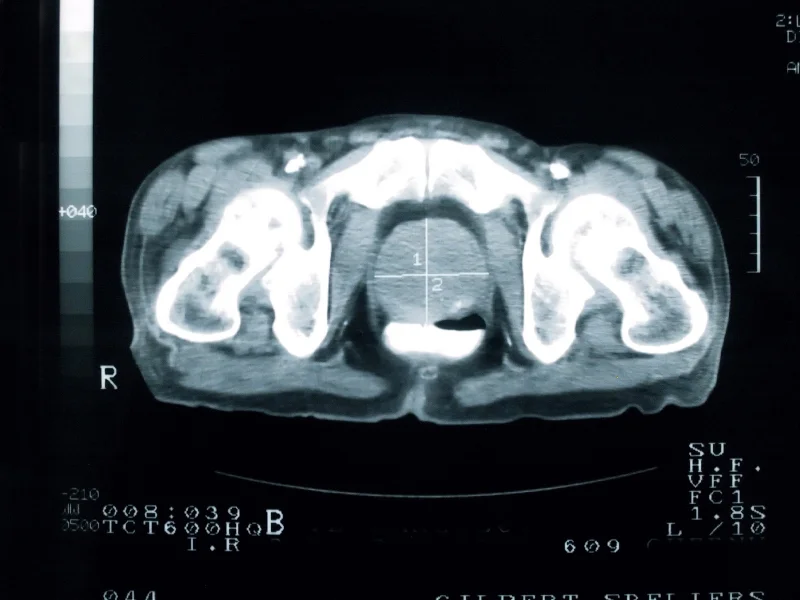

How the Gleason score grades aggressiveness of prostate cancer

/The primary grade and secondary grade will be a number ranging from 1-5. This is based on how much the cells in the cancerous tissue look like normal prostate tissue under a microscope which is called a Gleason system.